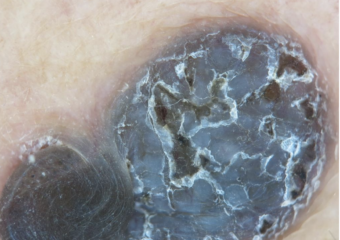

Basal cell carcinoma on the posterior torso. Photo: International Skin Imaging Collaboration at isic-archive.com

Basal cell carcinoma on the neck. Photo: International Skin Imaging Collaboration at isic-archive.com

Basal cell carcinoma on the anterior torso. Photo: International Skin Imaging Collaboration at isic-archive.com

Basal cell carcinoma on the anterior torso. Photo: International Skin Imaging Collaboration at isic-archive.com

Basal cell carcinoma on the anterior torso. Photo: International Skin Imaging Collaboration at isic-archive.com

Basal cell carcinoma presenting as an open sore on the ear. Photo: International Skin Imaging Collaboration at isic-archive.com

Basal cell carcinoma presenting as a pink growth. Photo: International Skin Imaging Collaboration at isic-archive.com

Basal cell carcinoma on the leg. Photo: International Skin Imaging Collaboration at isic-archive.com

A small pink growth with a slightly raised, rolled edge and a crusted indentation in the center. (BCC)